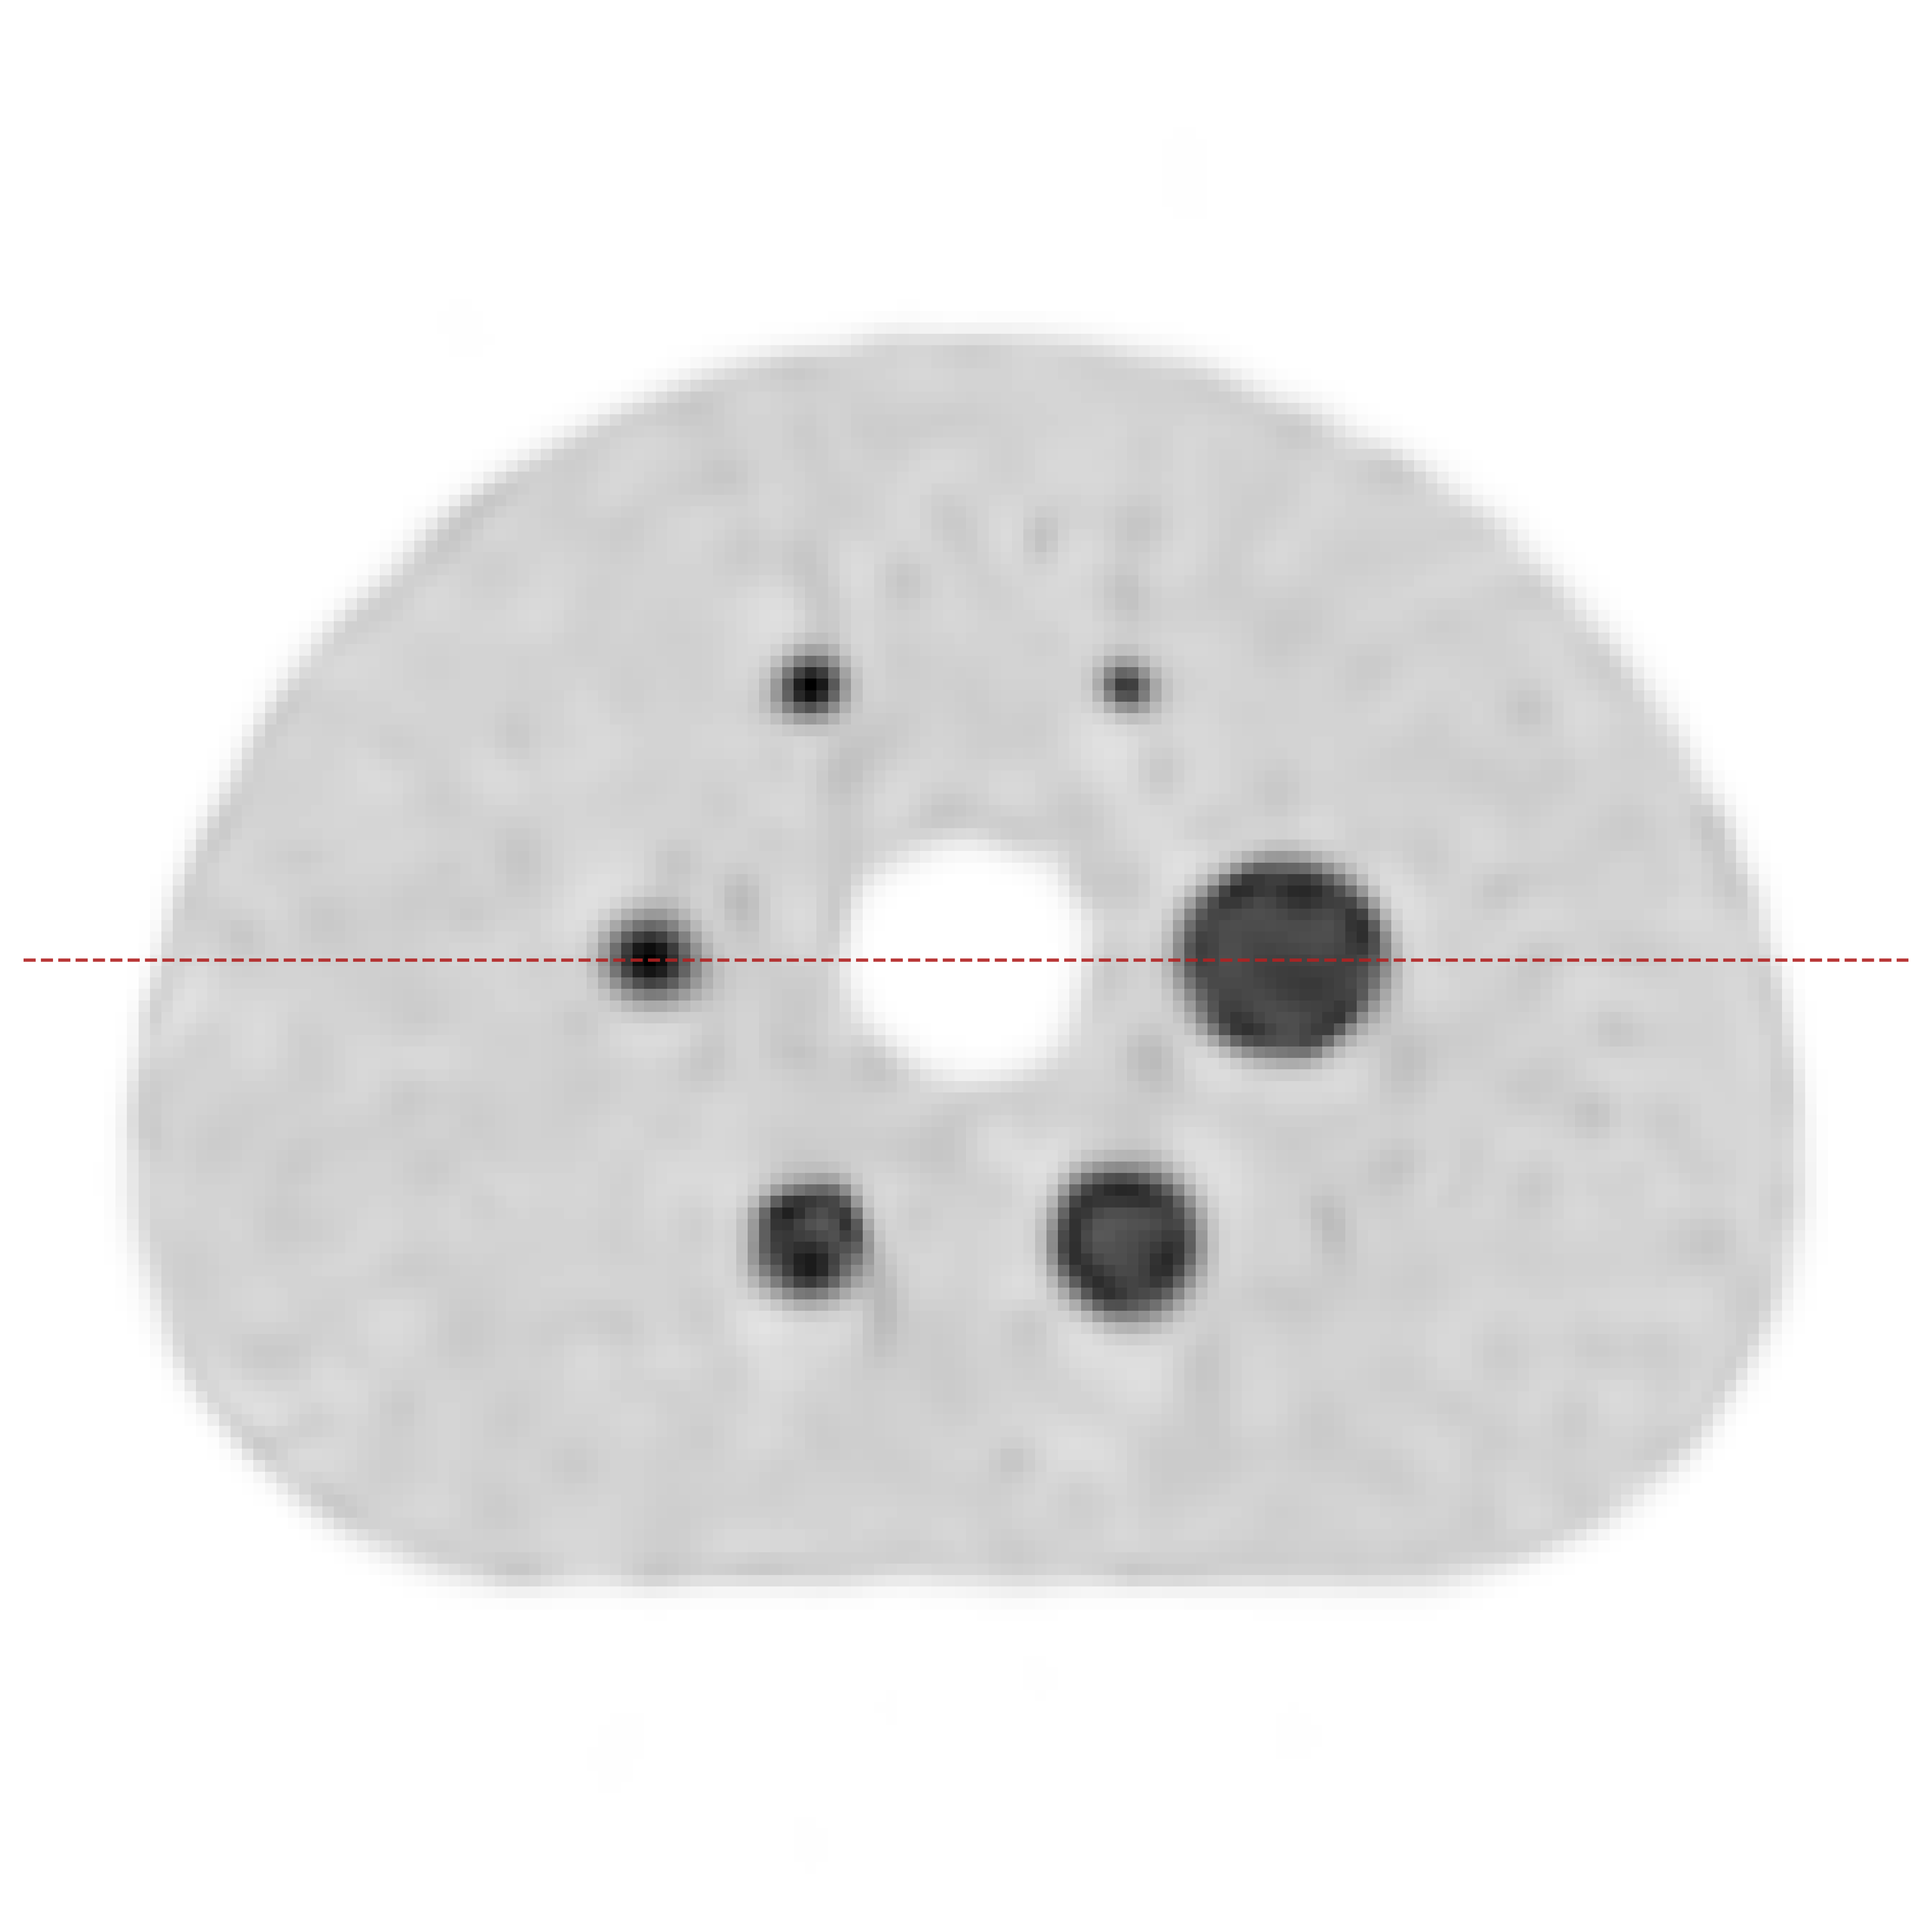

Point sources are commonly used to measure the spatial resolution of PET systems [16], since spatial resolution is typically defined as the FWHM of the Point Spread Function (PSF) [2] and is calculated from the line profile through a reconstructed image of a point source in air. The results of the three-point-source Monte Carlo simulation are shown in Fig. 5. All reconstructions were produced by our method; Fig. 5(a) and Fig. 5(b) show results without and with arc correction, respectively. Here we also measured the FWHM of the three point sources. For the non-arc case, the FWHMs are 3.43, 3.69, and 5.56 pixel, respectively. For the arc-corrected case, they are 3.45, 3.82, and 4.56 pixel, respectively. Since the three point sources were set to the same activity, their reconstructed values should be similar. The arc-corrected reconstruction yields values that are closer to each other. The results show that applying arc correction can improve spatial resolution and quantitative accuracy [9, 19], especially for sources far from the center of field of view.